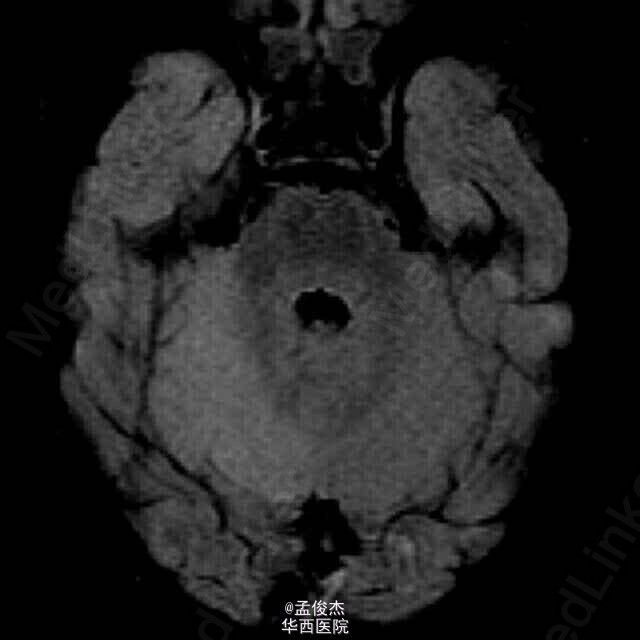

患儿女,33个月大,发热3天,体温最高102°F,伴有心动过速,130次/分。阵发性癫痫一天,伴有尖叫,双手紧握,双眼上翻,症状持续几秒到一分钟,仅在睡眠中发生。患儿在睡眠中易醒,既往有轻度哮喘。查体,黏膜干燥,余者无明显异常,血常规电解质水平检查无异常,血气分析示碳酸氢盐12 mmol/L,血糖69 mg/dL,尿中有大量酮体;脑脊液检查显示每立方毫米2个白细胞,1040个红细胞。头颅CT无明显异常,腹部超声无明显异常。 予总量为40 mL/kg 的生理盐水治疗心动过速,患儿心率恢复正常。使用万古霉素,头孢曲松钠治疗可能存在的败血症。 住院期间患者的癫痫持续发作,逐渐发展为吞咽困难,无法说话和右侧肢体无力。血尿脑脊液培养结果为阴性,停止输入抗生素。脑电图无异常。MRI示小脑右半球T2信号增高提示小脑水肿。碳酸氢盐升高至18 mmol/L,尿液中持续存在大量酮体。酮硫解酶 基因检测正常。CT检查示回肠末端的不规则增厚,管状软组织突出入盲肠。病毒PCR示患儿H1N1感染。 最终诊断为病毒性脑炎。患儿接受奥司他韦治疗后,明显好转,若干月后出院。 病毒相关脑炎与甲型流感关系最为密切,常见于5岁儿童。感染一周后出现症状,死亡率为37%。流感病毒导致的脑损伤并不经常表现为脑炎而是表现为代谢障碍,酮体增加,小脑水肿。